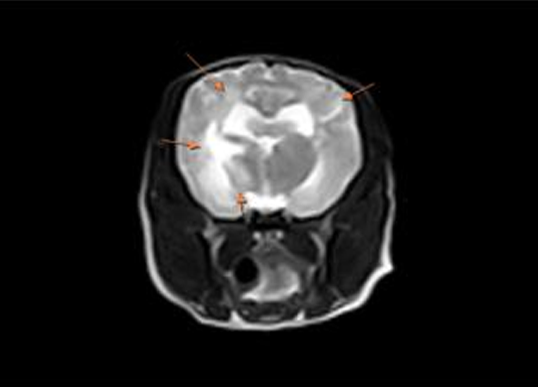

신경내과는 동물의 중추신경(뇌,척수)과 말초신경과 관계되는 질환을 진단하고 치료하는 분야입니다. 신경계 질환은 발작, 마비, 운동장애, 치매와 같은 증상을 보일 수 있습니다.

최근 노령 반려동물의 증가로 각종 퇴행성 질환, 신경계 종양으로 인한 신경환자가 많아지고 있습니다. 이에 대한 진단과 치료에 대한 연구가 꾸준히 진행되고 있습니다. 건국대학교 부속 동물병원은 전문적인 진단과 치료를 하고자 최선을 다하고 있습니다.

증상 치료 뇌수두증, 육아종성 뇌수막염, 괴사성 뇌수막염, 뇌종양, 중증근무력증, 말초신경병증 등 신경검사, 뇌척수액검사, 뇌파검사, 근전도검사 등